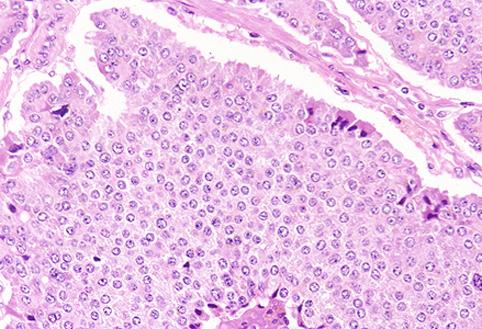

카시노이드종양 (소장)

회맹부에 끼여든 회맹말단부의 소장 카시노이드

[Image-ID:4228]

질환(병리주체)의 분류

카시노이드종양/

부위(장기별)

소장/회장

검사방법

마이크로

종양의 최대경(밀리미터)

25~29